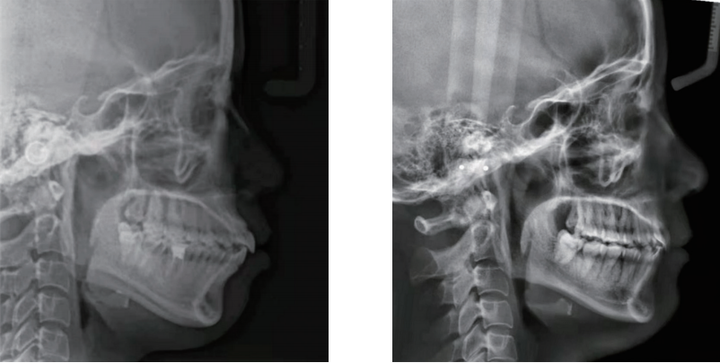

1、颌骨形态发育

一般来讲我们会观察下颌骨的x光片,从头侧片上就能看到髁状突颈部的形态。

(1)如果髁状突颈部形态比较细,那它的一定长得不好;

(2)如果这个髁状突颈部形态长得比较粗,那下颌骨发育的就会好。

2、下颌升支长短

一般来讲下颌升支越宽,下颌骨发育也就越好,升支越窄,下颌发育就越不好。

3、升支的角度

一般下颌升支越往前往下,这个人的下巴是往前出去的,这种状态下颌骨发育也不好。

相对来讲垂直向下会更好一些,但也不能太垂直向下,太垂直向下发育就会发展成国字脸了,也就是低角面型。

在下颌角靠后的这个地方,如果你摸到一个深沟,我们叫角前切迹,有角前切迹的发育的也不好,没有的才是颌骨发育比较好的。

5、下前牙骨壁薄厚程度

当下前牙骨壁越薄,下颌骨的正中联合发育的也不好,骨壁越厚,下颌发育越好。

所以我通常会根据这几个结构,来看下颌骨的发育的程度,比如说:越是均角、越是低角面型,这种下颌骨如果引导前伸,这一定改善是最好的。